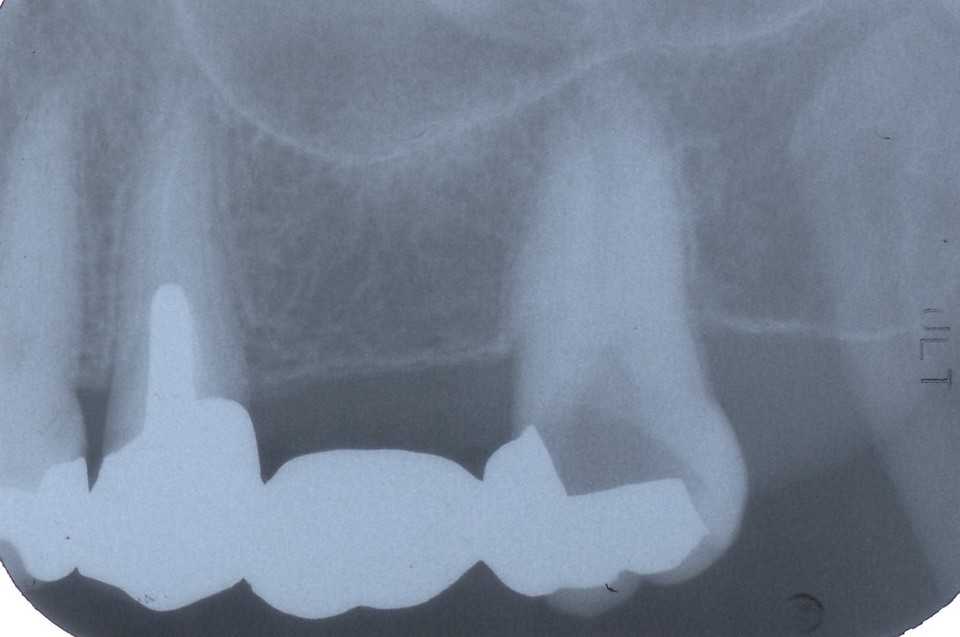

ストリップスを使わない隣接面CR7.1(外傷性歯牙破折)

60代女性、右下7、外傷性歯冠破折前回と同じ方、就眠時の食いしばりで歯が欠けて、そこから2次カリエスになったと思われる。CRで再建することを推奨されている方でも、ストリップスを使わないということは有り得ないというのが一般的な考え方です。しかしここではストリップスを使えないもしくは困難な症例でもなんとかCRで再建できるのだという症例を集めています。コツはフロアラブルレジンの濡れ特性と表面張力のバランスを考えながら積層法を使うということです。まぁ、慣れれば誰でもできるようになると思う。シリコンシーラーを使う時の感覚に近いものがあります。フィニシングラインにCRを出しながら(出すだけで)形を作っていきます。 クリック↓レントゲン写真ではこれも前医は頑張った様でギリギリ歯髄は保存してあると思う。4年前の画像、まだ大丈夫だった。レントゲン写真鏡像今回の治療過程、時系列でどうぞ横方向にもクラックができていて、インレーに破折片が付いてきた。虫歯を除去していく裏装のレジンも除去露髄はしていないようだ。α-TCP+3MIXで覆罩1次CR咬合調整してフロスが通るかどうか確認して終わる。